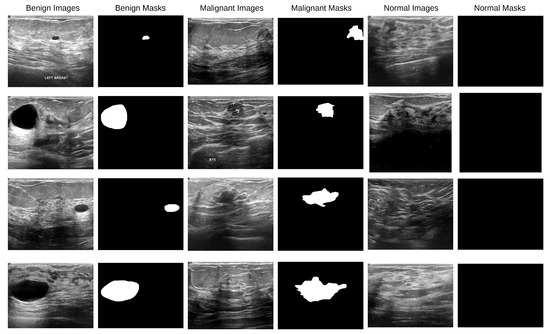

BAS-SegNet: A Boundary-Aware Sobel-Enhanced Deep Learning Framework for Breast Cancer and Skin Cancer Segmentation

by Md Sabbir Hosen and Hongxin Zhang

Electronics 2026, 15(1), 75; https://doi.org/10.3390/electronics15010075 - 24 Dec 2025

Early diagnosis of breast and skin cancers significantly reduces mortality rates, yet manual segmentation remains challenging due to subjective interpretation, radiologist fatigue, and irregular lesion boundaries. This study presents BAS-SegNet, a novel boundary-aware segmentation framework that addresses these limitations through an enhanced deep [...] Read more.

Early diagnosis of breast and skin cancers significantly reduces mortality rates, yet manual segmentation remains challenging due to subjective interpretation, radiologist fatigue, and irregular lesion boundaries. This study presents BAS-SegNet, a novel boundary-aware segmentation framework that addresses these limitations through an enhanced deep learning architecture. The proposed method integrates three key innovations: (1) an enhanced CNN-based architecture with a switchable feature pyramid interface, a tunable ASPP module, and consistent dropout regularization; (2) an edge-aware preprocessing pipeline using Sobel-based edge magnitude maps stacked as additional channels with geometric augmentations; (3) a boundary-aware hybrid loss combining Binary Cross-Entropy, Dice, and Focal losses with auxiliary edge supervision from morphological gradients. Experimental validation on the BUSI breast ultrasound and ISIC skin lesion datasets demonstrates superior performance, achieving Dice scores of 0.814 and 0.935, respectively, with IoU improvements of 16.3–22.4% for breast cancer and 8.8–11.5% for skin cancer compared with existing methods. The framework shows particular effectiveness under challenging ultrasound conditions where lesion boundaries are ambiguous, offering significant potential for automated clinical diagnosis support. Full article

Show Figures

Figure 1